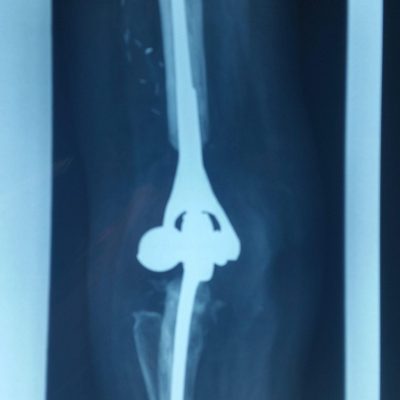

Total Elbow Replacement (TER)

TER has been used to treat patients with Rheumatoid arthritis in the past. As the medical management of Rheumatoid arthritis has improved over the last few decades, we have seen an overall reduction in patients requiring joint replacement. Patients with osteoarthritis or post-trauma now form an increasingly larger number of patients having TER, forming 70% of TER’s performed in Australia in 2019. The procedure involves removing the damaged joint surfaces and replacing the joint and inserting stems into the bone which are secured with cement. Overall 10 year survival in is 80-90%.

Specific risks of Total Elbow Replacement include, infection, fracture, nerve injury, loosening and dislocation.